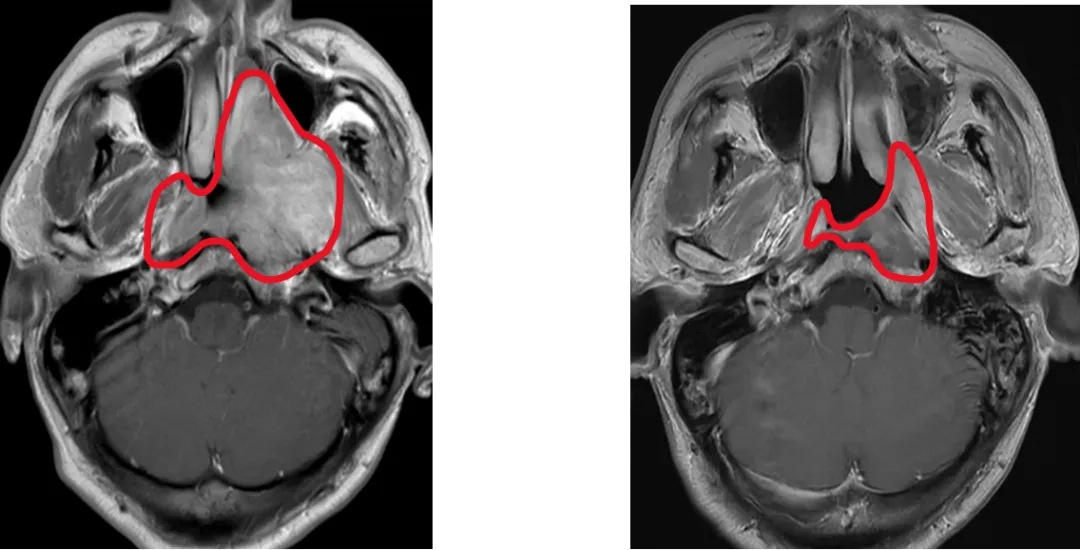

Ç㸲ʽÁ¢Ò죺ÌÜд¾«×¼·ÅÁÆÐ±ê×¼

±ÇÑʰ©¸ß·¢ÓÚÖйú£¬£¬£¬Ð·¢²¡ÀýռȫÇò47%¡£·ÅÉäÖÎÁÆÊDZÇÑʰ©µÄ¸ùÖÎÊֶΣ¬£¬£¬µ«ÖÐÍíÆÚ»¼ÕßÐèÒªÔÚ·ÅÁÆÇ°½ÓÊÜ»¯ÁÆ£¬£¬£¬·ÅÁÆÇ°»¯ÁÆÊ¹90%»¼ÕßÖ×ÁöËõС£¬£¬£¬¶ø¼ÈÍù¹ú¼ÊÖ¸ÄÏÍÆ¼ö·ÅÁÆÕÕÉ乿ģÈÔÐè°üÀ¨»¯ÁÆÇ°Ö×Áö¾ÞϸÁýÕֵĹæÄ££¬£¬£¬µ¼ÖÂÖÜΧÕý³£×éÖ¯£¨ÈçÄÚ¶ú¡¢¡¢ÈùÏÙ£©½ÓÊܸ߼ÁÁ¿·øÉ䣬£¬£¬Òý·¢ÌýÁ¦ËðÉË¡¢¡¢¿Ú¸ÉµÈ²»¿ÉÄæ¸±×÷Ó㬣¬£¬ÑÏÖØÓ°Ï컼ÕßÉúÑÄÖÊÁ¿¡£

Ϊ´Ë£¬£¬£¬Âí¿¥ÔºÊ¿ÍŶÓÕö¿ªÓйØÑо¿£¬£¬£¬½ÓÄÉÁ˹ú¼ÊͨÓõıê×¼¶àÖÐÐÄ¡¢¡¢Ëæ»ú¡¢¡¢Æ½ÐбÈÕÕÉè¼Æ£¬£¬£¬ÄÉÈë445ÀýÖÐÍíÆÚ±ÇÑʰ©»¼Õߣ¬£¬£¬Ëæ»ú·ÖΪÁ½×飺»®·Ö»ùÓÚ»¯ÁƺóºÍ»¯ÁÆÇ°Ö×Áö¹æÄ£¾ÙÐзÅÁÆ¡£Ö÷ÒªÖÕµãΪ3Äê¾Ö²¿ÇøÓòÎÞ¸´±¬·¢ÑÄÂÊ£¬£¬£¬´ÎÒªÖÕµã°üÀ¨¶¾¸±·´Ó³ºÍÉúÑÄÖÊÁ¿¡£

ÕâÏî¶àÖÐÐÄIIIÆÚÁÙ´²ÊÔÑé֤ʵ£¬£¬£¬½öÕÕÉ仯ÁƺóµÄÖ×Áö¹æÄ££¬£¬£¬²¢Ã»ÓÐÔöÌí¸´·¢£¬£¬£¬È´ÏÔÖø½µµÍÁ˶¾¸±·´Ó³£¬£¬£¬ÏÔÖø¸ÄÉÆ»¼ÕßÉúÑÄÖÊÁ¿£¬£¬£¬Ê¹ÎÒ¹ú±ÇÑʰ©ÕïÁÆÊµÏÖ´Ó¡°±£ÉúÑÄ¡±µ½¡°ÓÅÉúÑÄ¡±µÄ¿çÔ½Ê½Í»ÆÆ¡£3Äê¾Ö²¿ÇøÓòÎÞ¸´±¬·¢ÑÄÂÊ´ï91.5%£¨Óë¹Å°åÁÆ·¨³Öƽ£©£»ÑÏÖØ·ÅÉäÐÔ¿ÚÇ»ð¤Ä¤Ñ×½µµÍ4³É£¬£¬£¬ÍíÆÚÑÏÖØÖжúÑ×±¬·¢ÂÊÈñ¼õ5³É£¬£¬£¬¿Ú¸ÉÖ¢×´¸ÄÉÆ6³É£»ÕûÌ念½¡×´Ì¬¡¢¡¢ÌåÁ¦×´Ì¬¡¢¡¢ÇéÐ÷¹¦Ð§ÏÔÖø¸ÄÉÆ£¬£¬£¬¿Ú¸É¼°ÍÙÒºð¤³íÖ¢×´¼õÇá¡£